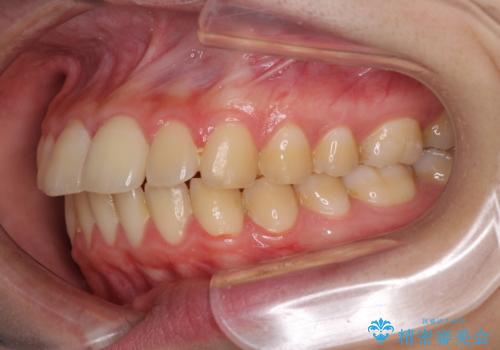

口元が出てるの気になる、引っ込めたい ワイヤーによる抜歯矯正で横顔の改善

口元を下げて口唇を閉じやすくする場合、抜歯矯正をお勧めさせていただくことが多いです。

治療前には必ず患者様とよく相談させていただき、どのようなゴールにするか、それにはどんな治療が必要かをご理解していただいたうえで、治療を開始いたします。